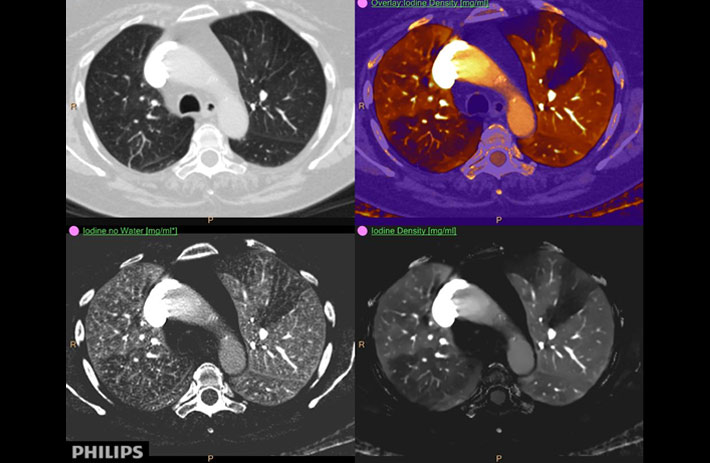

Mit dem Spektral-Detektor-CT werden Spektraldaten automatisch bei jedem Scan erfasst. Die Informationen stehen jederzeit auf der Scankonsole, der CT-Workstation sowie an jedem PACS-Arbeitsplatz zur Verfügung, sodass es nicht notwendig ist, den Patienten erneut zu scannen, bspw. wenn initial zufällige Anomalien festgestellt wurden. Dadurch profitieren Anwender durch eine höhere Diagnosesicherheit und weniger Nachuntersuchungen auf anderen bildgebenden Systemen. Unsere Fallsammlung zeigt, welchen klinischen Mehrwert der Spektral-Detektor-CT in unterschiedlichsten Anwendungsbereichen in der klinischen Routine bringt. Jede Woche gehen neue Fälle live.